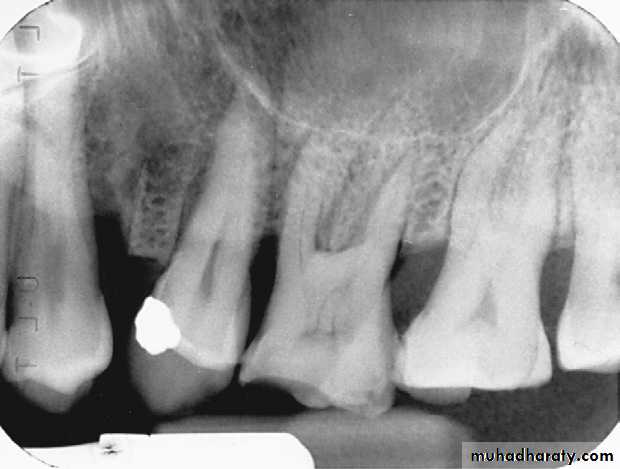

horizontal bone loss:

Bone loss occurs in a plane parallel to CEJs of adjacent teeth.

Horizontal bone lossis used to describe the radiographic appearance of the loss of bone height in the region of several adjacent teeth. Horizontal bone loss may be classified as localized or generalized, depending on the regions involved.